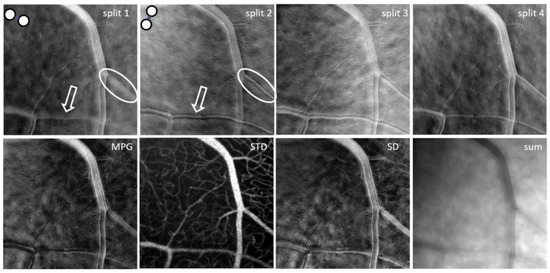

A significant problem with split detection is its directionality artefact. If a blood vessel is parallel with the offset/split direction, it cannot be seen, as illustrated in the split-1 image within the white oval in Figure 3. However, the vessel edges can be distinguished very well if the offset/split direction is perpendicular to the vessel, as within the white oval in the split-2 image of Figure 3. Similarly, the white arrows point to crisp wall details of a blood vessel in the split-2 image and to blurred details in the split-1 image of Figure 3. It should therefore be expected that if only one split is used, there will be structures that cannot be visualized and one needs two orthogonal split directions simultaneously for complete visualization of all retinal structures, independent of their orientation.

Figure 3.

Mean images for the four splits, magnitude of the phase gradient (MPG), mean of the four split standard deviations (STD), standard deviation among the four simultaneous offsets (SD), and sum derived from the four offset images shown in Figure 2.

Split-detection analysis can be performed using multiple combinations of the four offset images. Two orthogonal split images are generated for fiber pairs 1–3 (split-1) and 2–4 (split-2) as illustrated in Figure 3. Two additional split images are obtained by first adding adjacent fibers, for example 1 + 2 and 3 + 4, and then performing subtraction divided by the sum of the two sums (1 + 2 − 3 − 4)/(1 + 2 + 3 + 4) for a near vertical split (split-4); similarly, (1 − 2 − 3 + 4)/(1 + 2 + 3 + 4) provides an near horizontal split (split-3). Therefore, four split images can be obtained; for the horizontal, vertical, and diagonal (±45 deg) directions of the offset apertures and given their directionality, each of the four split images highlights boundaries such as blood vessel walls along different directions. In addition to this, we can calculate the mean and standard deviation for each split similar to individual offsets and the mean of the four split standard deviations (STD).

The horizontal and vertical splits are similar to the half aperture, as in [24]. They can also be interpreted as phase derivatives along the horizontal and vertical directions. As mentioned above, the idea of split detection was derived from differential phase-contrast microscopy; therefore, using these orthogonal derivatives, one can directly calculate the magnitude of the phase gradient (MPG) as the square root of the sum of squared orthogonal derivatives or reconstruct the phase [31,32,33].

The standard deviation (SD) among the four simultaneous offsets, a concept first introduced in [26], highlights the differences illustrated in these images, which are mostly visible at the blood vessel boundaries, due to the directionality diversity provided by such a multi-offset detection arrangement. The sum of the four offset images in a ring-detection configuration (sum) combines all detected forward-scattered light while rejecting the direct backscattered light, which is simultaneously detected through the central fiber in the confocal image (SLO). Movies for monitoring temporally dynamic processes such as blood flow or cell migration, as well as mean and standard deviation images for each of the four splits, SD, sum, STD, and MPG, can be generated through our analysis. An example of all these mean images is shown in Figure 3. Also as an example, Video S1 (Supplementary Materials) shows the stack of split-4 images that could be registered and aligned after removing the images distorted by involuntary eye motion. The video illustrates the flow of blood cells through the capillaries that generates the motion contrast highlighted in the STD image in Figure 3.

It should be noted here that SD, STD, sum, and MPG are all isotropic, direction-independent, as they were derived from all four offset images and are therefore directionally diverse. STD reveals maps of capillaries with much better contrast than those in other imaging modalities and in a mode similar to OCTA. STD can also be used to segment the flow location in large vessels and to quantify the inside diameter of the vessels.